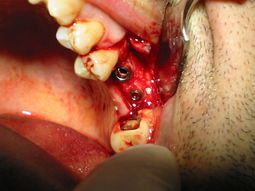

La sequenza fotografica mostra l'inserimento di due impianti con rialzo del seno mascellare:

111-1172_IMG.JPG

..si tratta di due impianti conici del diametro 4,1 e di lunghezza 10...